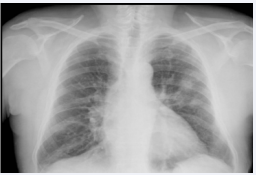

The autoimmunity study revealed antinuclear antibodies negative, Perinuclear Anti-Neutrophil Cytoplasmic Antibodies (p-ANCA) negative and cytoplasmic antineutrophil cytoplasmic antibodies (c-ANCA) positive with a titer of 99 Ui/ml. During admission, the patient began with hemoptysis, so a chest x-ray was performed that revealed bilateral pulmonary infiltrates in middle fields, although predominantly left (Figure 1).

Figure 1 Chest x-ray with bilateral pulmonary infiltrates in middle  fields, although predominantly left.

Consequently, the Department of Pneumology was asked to realize a respiratory functional study with diffusion pulmonary carbon monoxide (DLCO) that showed an increase of 114%, confirming the diagnosis of pulmonary hemorrhage.